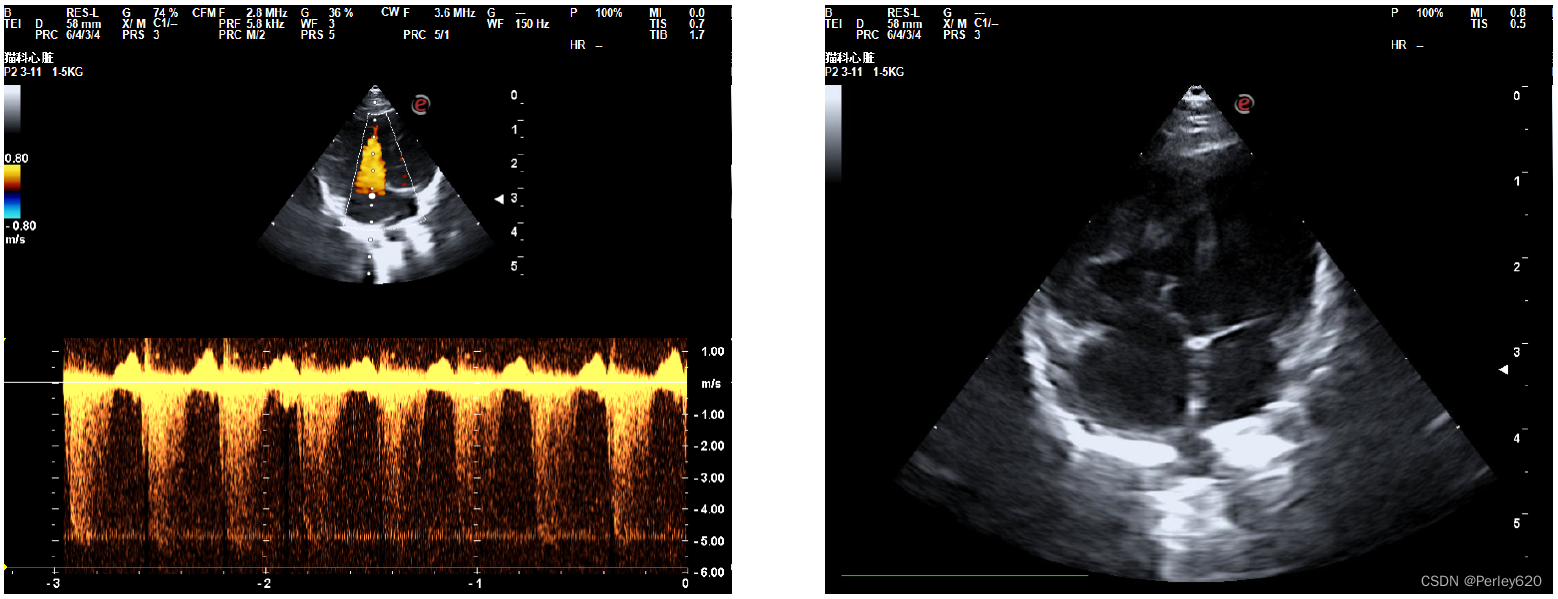

然后给她拍X光片,给她做彩超看心脏,宠物医院的院长看了半天,也没能确定是什么问题,她觉得是心脏左心室隔膜缺损,但没法给定论。

我们就去了宠物医院的总院,找了总院的院长做进一步的检查,最终是重度肺高压,就是很严重的一种病。

诊断的B超图